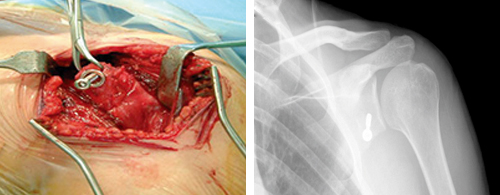

O labrum glenóide é uma estrutura fibrocartilaginea semelhante a um menisco que aumenta o contacto com a cabeça umeral estabilizando a articulação.

A Coifa dos Rotadores funciona como uma convergência de tendões, em redor da cabeça do úmero. Os tendões dos quatro músculos unem-se com a cápsula articular da articulação glenoumeral.